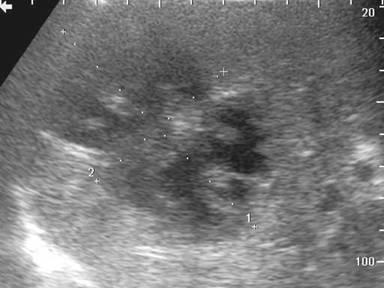

One day after admission, the occurrence of hematemesis urged repeated endoscopy, which revealed the fresh blood originating from the papilla of Vater (Figure 1). Endoscopic retrograde cholangiopancreatography was performed, demonstrating patent pancreatic duct and blind remnant of native common bile duct without communications between pancreaticobiliary tract and blood vessels. During the procedure few blood clots originated from the papilla of Vater. Multislice contrast computed tomography showed moderate enlargement of the pancreatic head with suspected hematoma (Figure 2), along with three splenic artery aneurysms, of 30 mm, 12 mm and 8 mm in diameter, in the distal arterial segment, as well as anastomotic stenosis of native and donor hepatic artery. However, contrast extravasation on visceral angiography was not detected (Figure 3). The embolization of the splenic artery aneurysms was judged unfeasible due to tortuosity of the splenic artery, wide neck of the major aneurysm and proximity of other two aneurysms to the splenic hilum. Supportive therapy stabilized the patient and gastrointestinal bleeding resolved. The patient was scheduled for surgery; however, subsequent development of hepatic artery thrombosis, resulted in multiple liver abscesses and septic episodes (Figure 4). On several occasions Enterococcus faecium and Klebsiella pneumoniae were identified from abscesses and blood cultures. Despite of a broad-spectrum antibiotic therapy and percutaneous drainage the fever persisted, although gastrointestinal bleeding did not reoccur. Three months later, the patient underwent liver re-transplantation and splenectomy. During the three past years of follow-up, the patient has remained uneventful.

Figure 4. Abdominal Doppler ultrasound showing a large liver abscess (85x52 mm). |